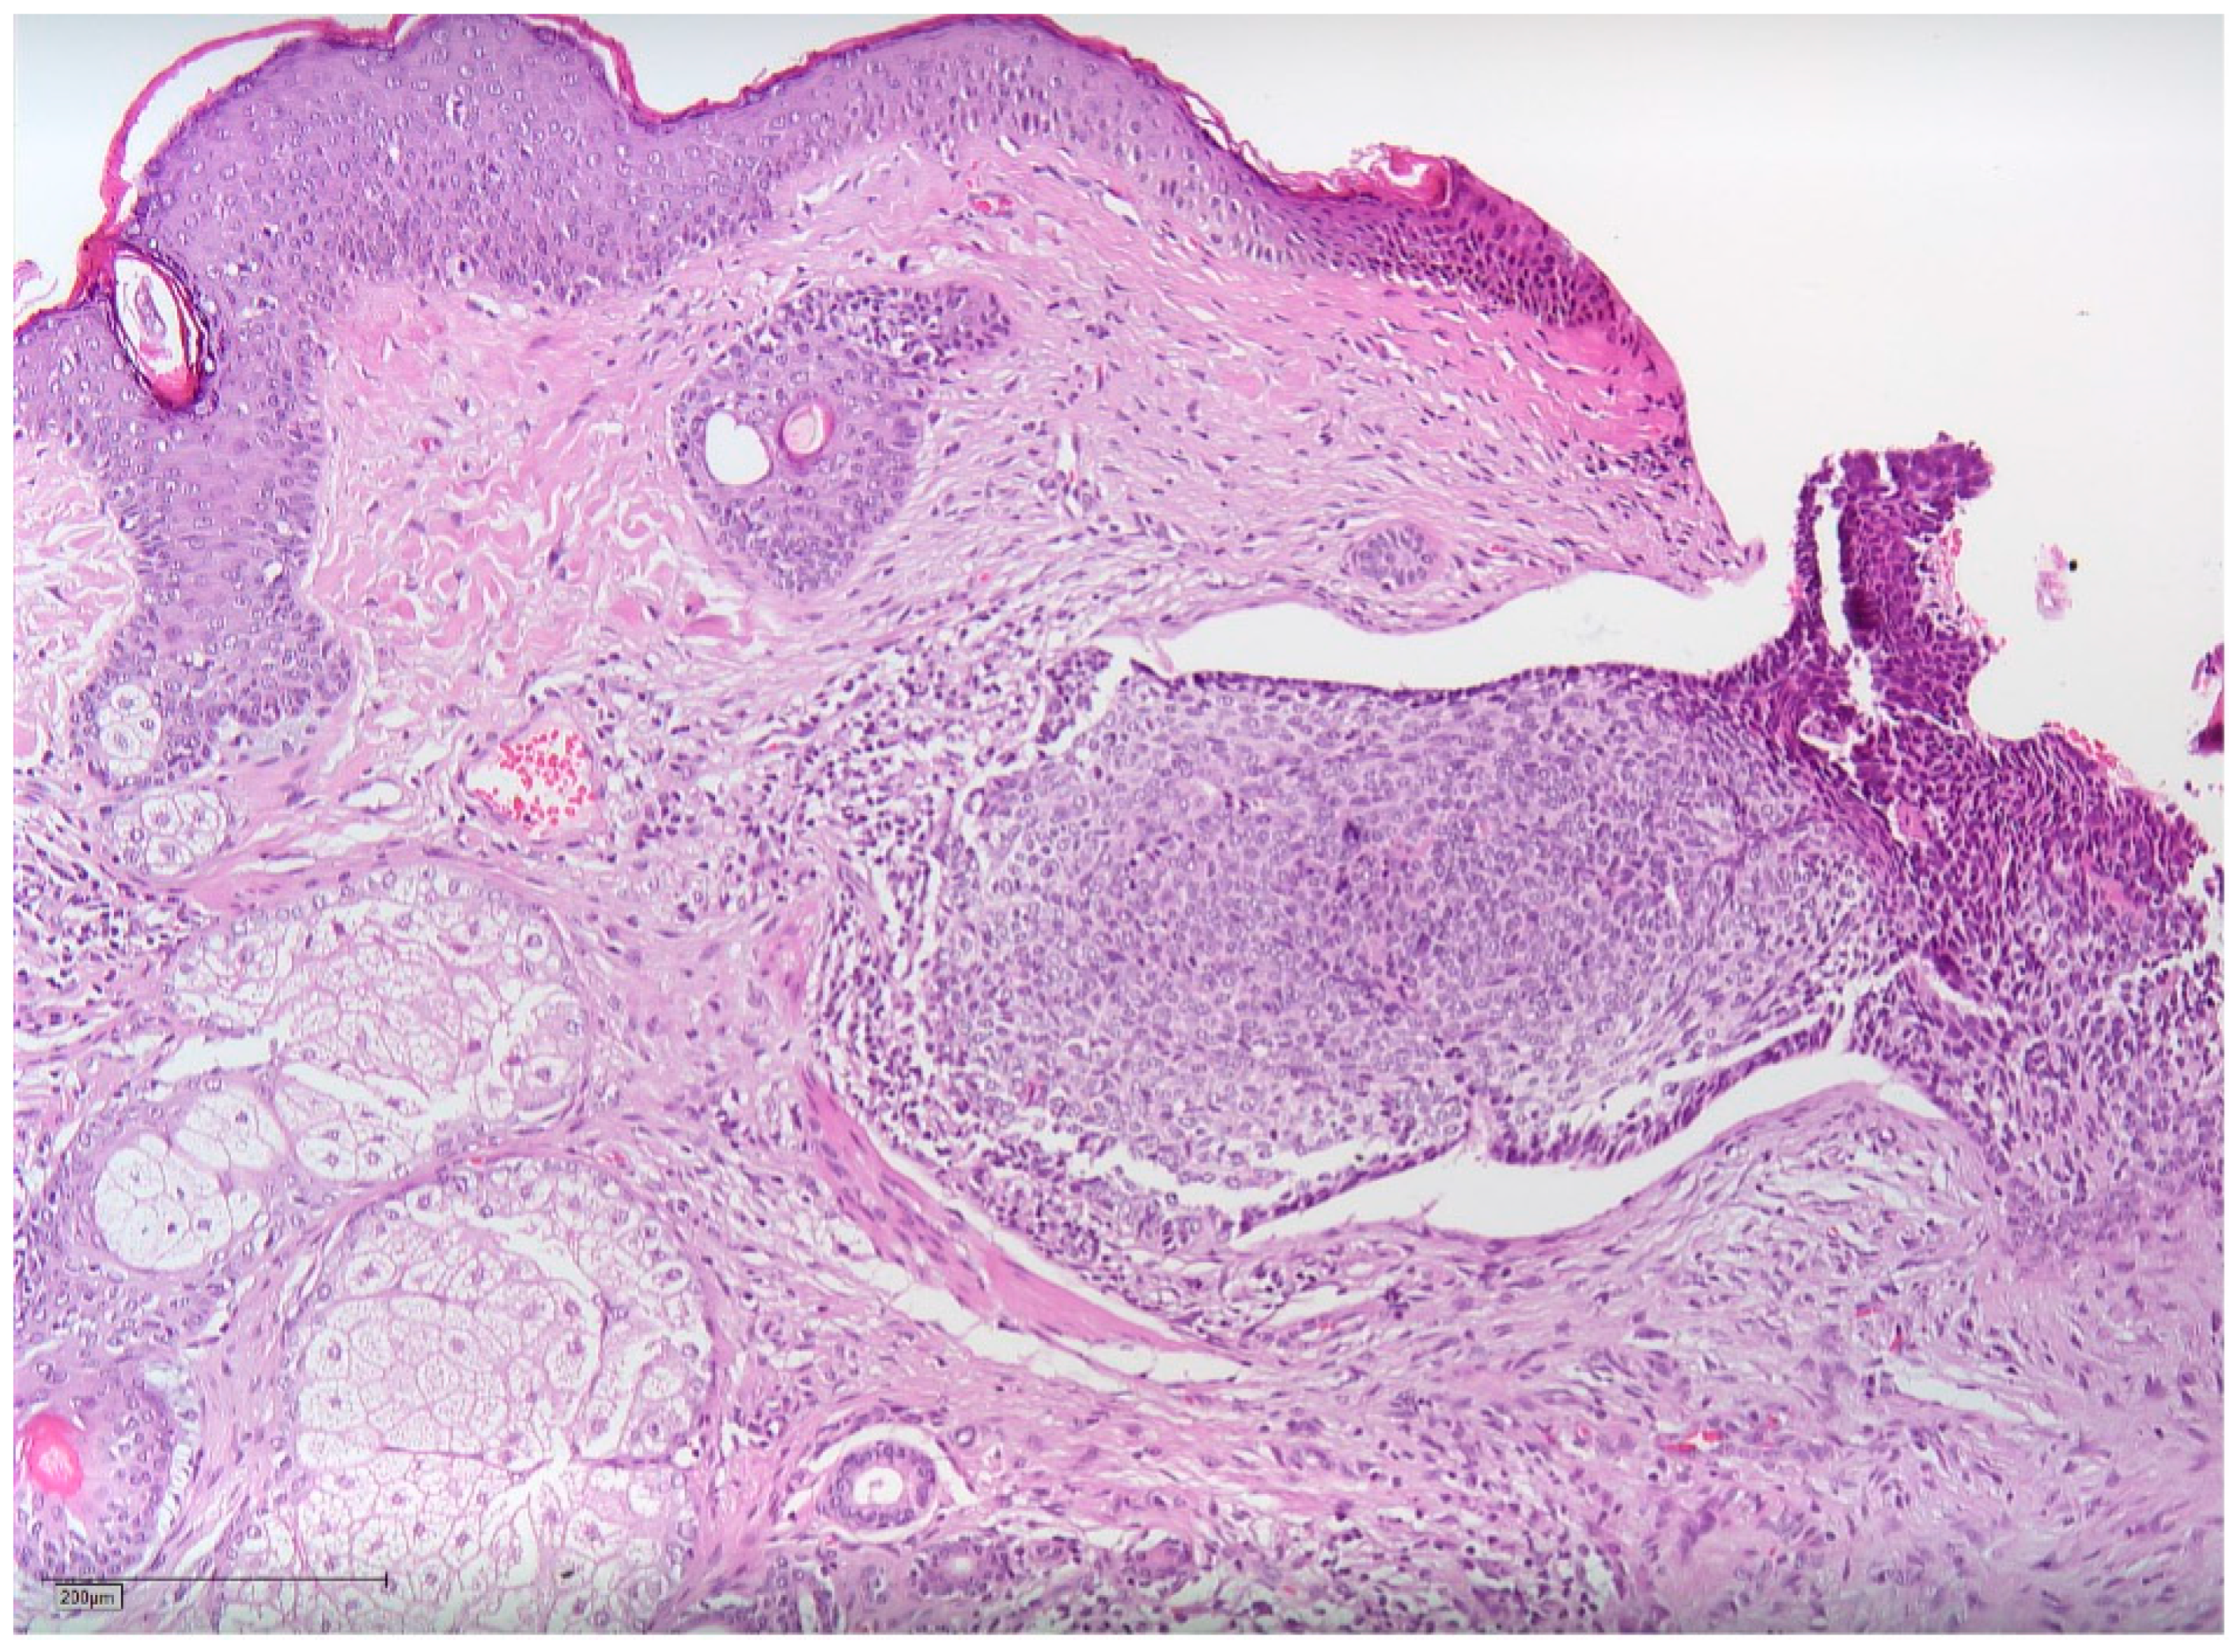

2. Case Report